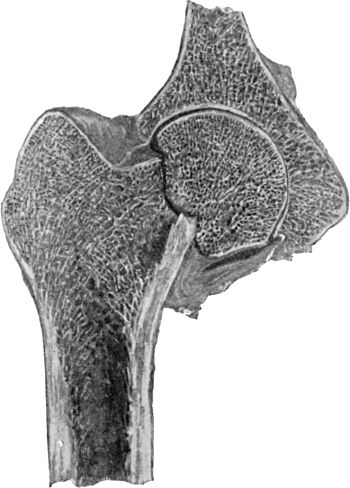

36.Backward Dislocation of Elbow in a Boy89

37.Bony Outgrowth in relation to insertion of Brachialis Muscle90

38.Radiogram of Incomplete Backward Dislocation of Elbow91